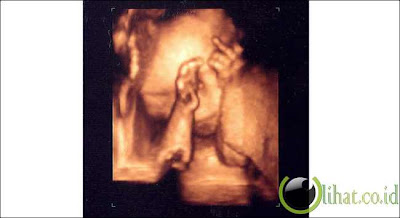

5.Raspberi

Ini luar biasa jelas foto diambil menggunakan teknologi 3-D. Bayi ini sudah meniup raspberry!